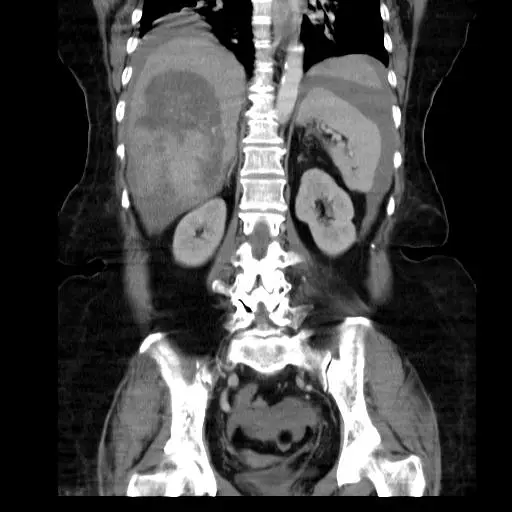

64歲女性,因急性右上腹部劇痛,掛急診求醫,腹部 CT 和血管攝影影像如附圖,則最可能的診斷為下列何者?

自發性肝腫瘤破裂導致急性腹痛與血性腹水的影像診斷

以動態對比增強CT與血管攝影判讀肝內高血管性病灶的特徵,區分肝細胞癌、肝內血管瘤、肝膿瘍或脂肪分布異常。

影像分析:

- 腹部CT(冠狀面):右肝葉可見一巨大、不規則邊緣的腫塊,內部呈現異質性密度。腫塊周邊可見高密度液體聚積,符合血性積液(血性腹水或皮下血腫);腫塊貼近肝包膜,疑似包膜缺損或破裂(“enucleation sign”)(ajronline.org)。